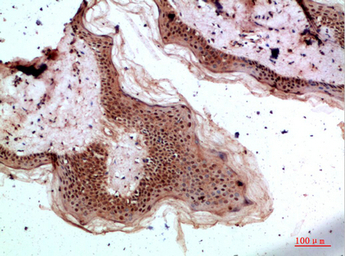

IHC-P analysis of human skin tissue using GTX34280 TPSD1 antibody.

Dilution : 1:200